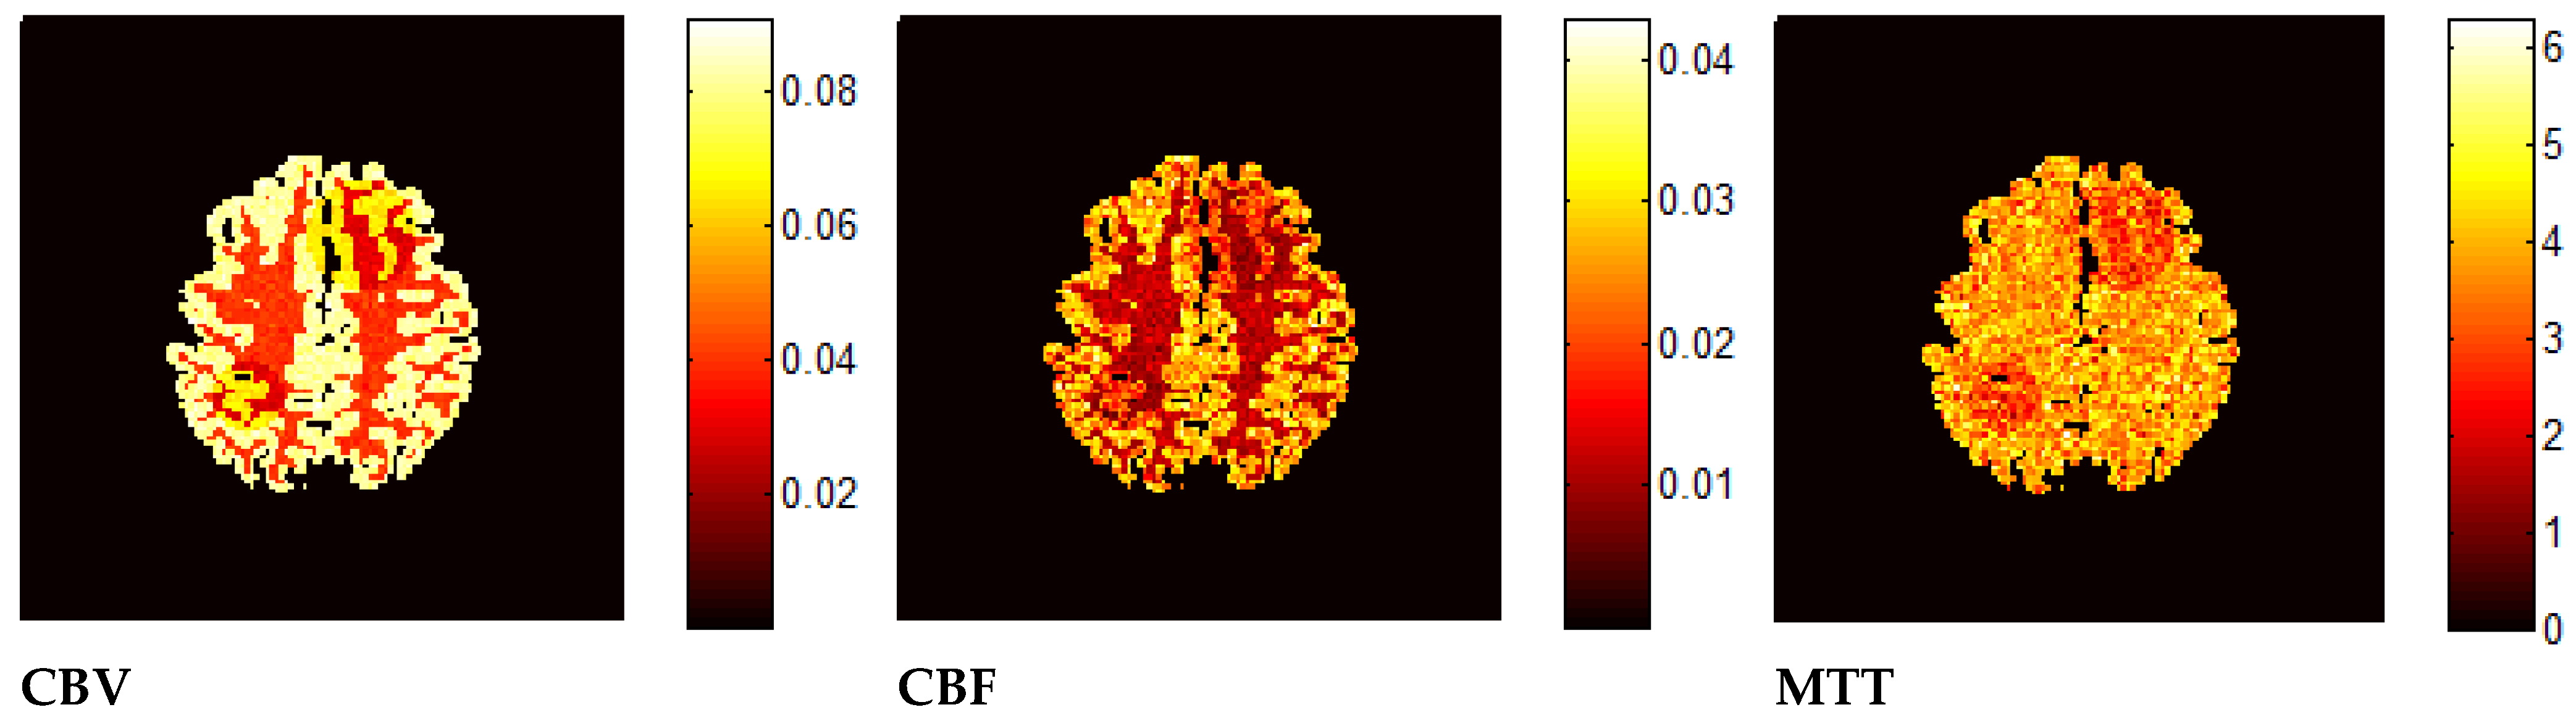

7. Results—Exemplary DSC-MRI Study Models

8. Discussion and Conclusions